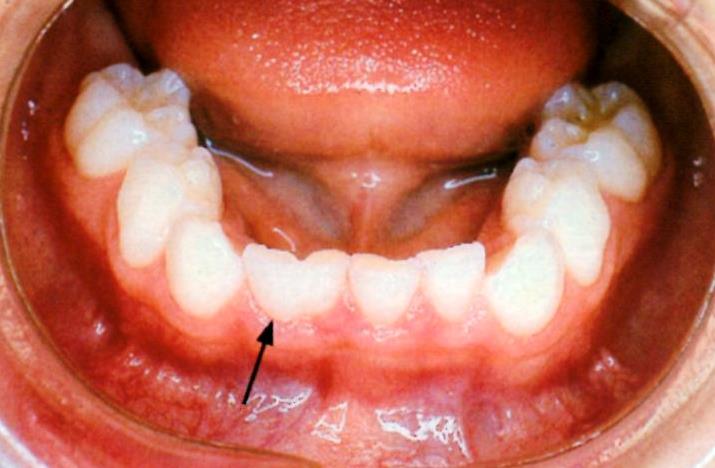

レーザー照射後 乳歯AとBの癒合歯

乳歯AとBの癒合歯 アップで

アップで